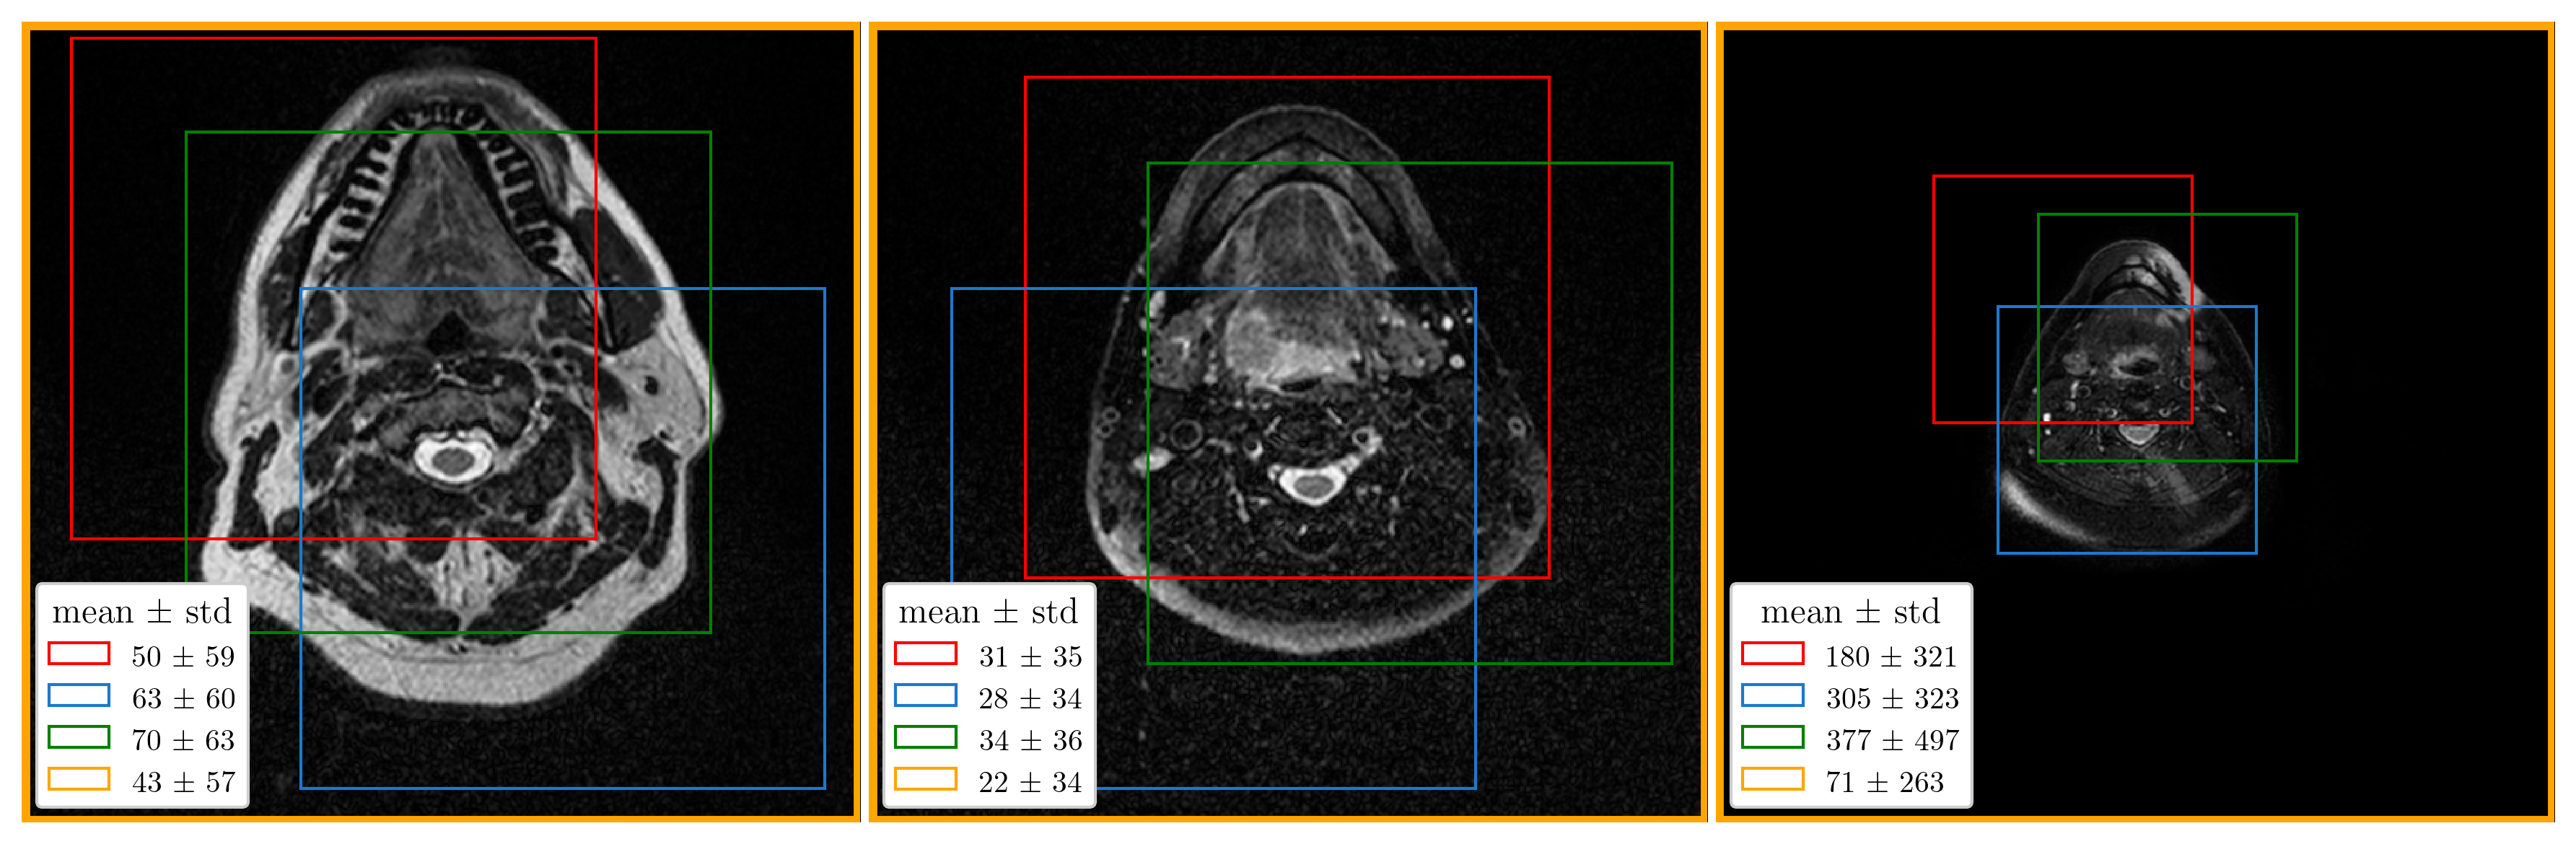

In contrast to CT, the intensity scale in MRI is not standardized and therefore intensity normalization is particularly important, especially when working with images from different MRI scanners [13]. Furthermore, input normalization is generally required to improve the convergence of optimization methods based on gradient descent. Z-score normalization, where all intensities are first shifted by the mean and then scaled by the standard deviation, works well in practice. However, this type of normalization is often applied with the mean and standard deviation computed on the entire image (image-wise normalization), even when training is carried out on image patches (see nnU-Net [2]). As a result, the intensity distribution in each patch (i.e., its mean and variance) depends on the patch location, which can significantly hinder the convergence of optimization methods. Similarly, the performance of models trained with patch-wise normalization (i.e., normalization is done after patch extraction) is affected by covariate shift [9, 8] when inference is performed on normalized images in a sliding window manner. Fig. 2 shows the differences in means and standard deviations between different patches and between images from the training set. To mitigate the effect of covariate shift, only patch-wise normalization was applied to the model inputs in both tasks (except for the binary masks in Task 2). At inference, the normalization was integrated directly into the sliding window approach.

In addition to the aggregated metrics in Table 1, Fig. 3 shows the results in terms of DSC, Precision, and Recall for individual data examples (i.e., patients) from the validation folds. A visual comparison of the predicted and ground truth masks for three different patients is provided in Fig. 4.